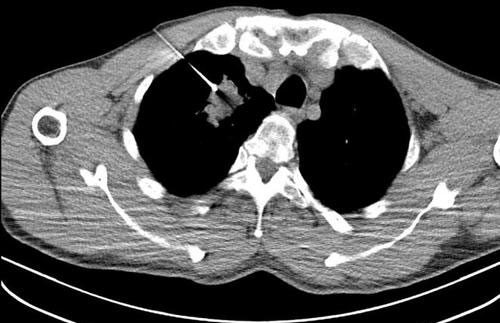

精准医疗,微创介入介入医学科是以影像引导的微创诊疗手术,专注于诊治各种疾病,致力于为患者提供安全、精准、高效的诊疗服务。科室依靠先进的CT等影像设备,通过微创技术手段开展肺结节、良恶性肿瘤等消融治疗,各部位穿刺活检及置管引流等,优势为不开刀、创伤小、恢复快、效果显著,提供契合现代医学“精准微创”理念的诊疗方案。一、微创消融治疗:肺结节、肺癌等病灶,可行微波/射频消融术及氩氦刀冷冻消融治疗,利用微创技术,不开刀,治疗肺结节及良恶性肿瘤等,肺结节、早期肺癌等可直接根治,达到与手术切除同等疗效,同时保留完整肺组织,不影响肺功能。中晚期患者可做到局部减瘤负荷联合全身靶向、免疫及放化疗等,双管齐下,效果优于单一治疗方案二、精准穿刺活检:利用微创穿刺技术直接取得病灶内部组织,…更多>>